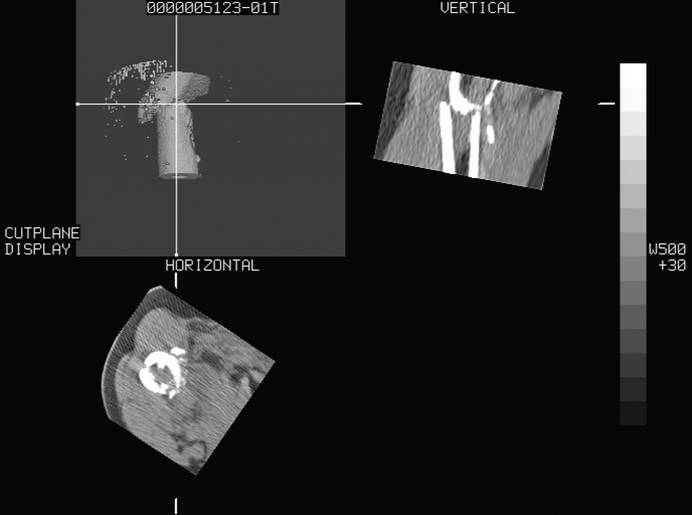

标题: CT16696:M53Y,左股骨上段骨折。 [打印本页]

标题: CT16696:M53Y,左股骨上段骨折。

左股骨上段粉碎性骨折

左股骨上段粉碎性骨折;建议上传骨窗看看是不是病理性的啊!

左股骨上段粉碎性骨折,不排除病理性骨折可能。

考虑骨肉瘤伴病理骨折

考虑:骨肉瘤伴病理骨折.

病理性骨折,考虑转移所致.